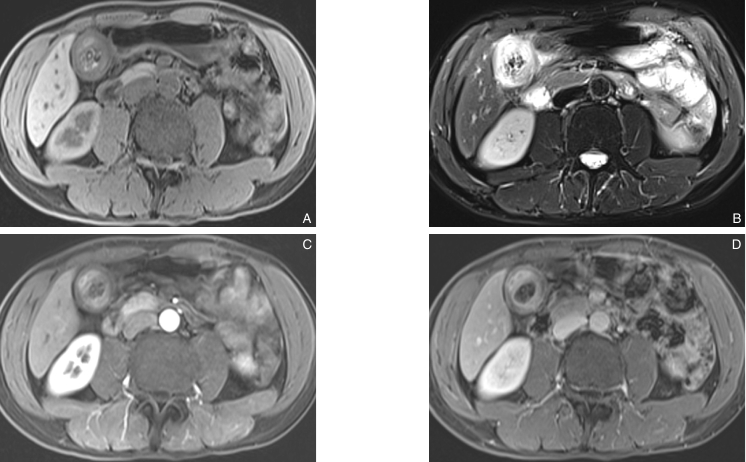

图1 磁共振检查显示胆囊壁明显增厚,信号不均,胆囊腔内呈低信号影,信号不均 A:T1WI;B:T2WI;C:动脉期;D:静脉期Fig.1